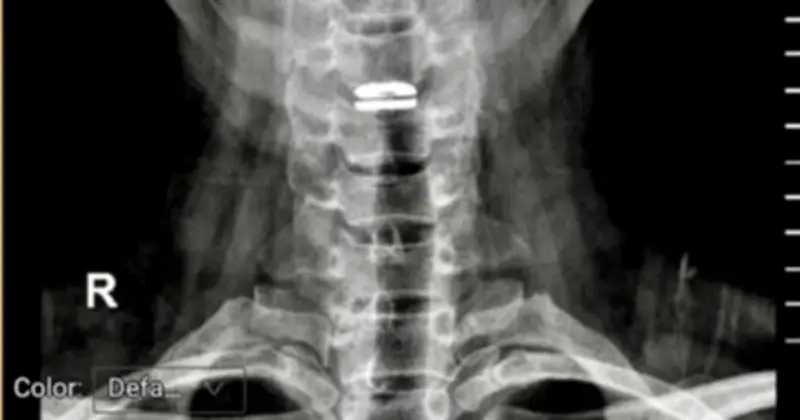

Tình trạng này khiến bệnh nhân không thể xoay người hay tự ngồi dậy. Chị mô tả: "Mọi tư thế đều rất đau, chỉ cần nhấp nhẹ là cổ đau không thể chịu nổi". Qua quá trình khám và chụp hình ảnh chẩn đoán tại Bệnh viện đại học Y dược, các bác sĩ chuyên khoa phẫu thuật cột sống đã xác định chị bị thoát vị đĩa đệm cổ, gây chèn ép tủy sống và có nguy cơ liệt cao nếu không được phẫu thuật ngay.

PGS-TS, bác sĩ Nguyễn Lê Bảo Tiến, Phó giám đốc Bệnh viện đại học Y dược, cơ sở Linh Đàm, người trực tiếp thực hiện ca mổ, cho biết trong quá trình phẫu thuật, bác sĩ phát hiện đĩa đệm cột sống cổ của bệnh nhân đã vỡ thành nhiều mảnh. Ông nhấn mạnh rằng nếu không mổ, không còn phương pháp nào để phục hồi đĩa đệm này về trạng thái bình thường. Do đó, bệnh nhân đã được thay thế bằng đĩa đệm cột sống cổ nhân tạo.